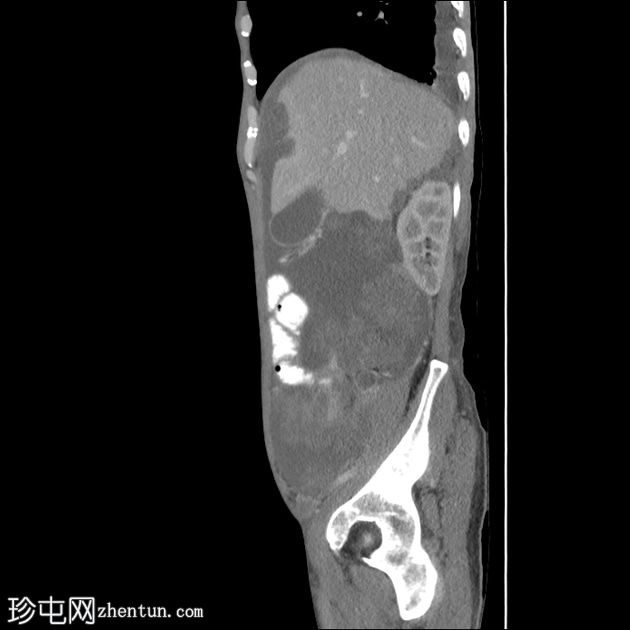

矢状位增强扫描(动脉期)

矢状位增强扫描(门静脉期)

大网膜和肠系膜内可见低密度、不均匀的腹膜积液,脏器表面呈扇形凹陷,尤其以肝脏和脾脏最为明显。

阑尾肿大,长 5.0 cm,直径 1.2 cm,大小符合,可能提示阑尾黏液性肿瘤

直肠穹窿可见一处厚度 1.2 cm、长 4.0 cm 的增强壁增厚。可见病灶周围及骶前淋巴结肿大,最大者直径 1.6 cm。

左下腹可见末端结肠造口。

可见双侧少量胸腔积液(右侧:1.0 cm;左侧:0.2 cm),右下后基底段被动性塌陷。